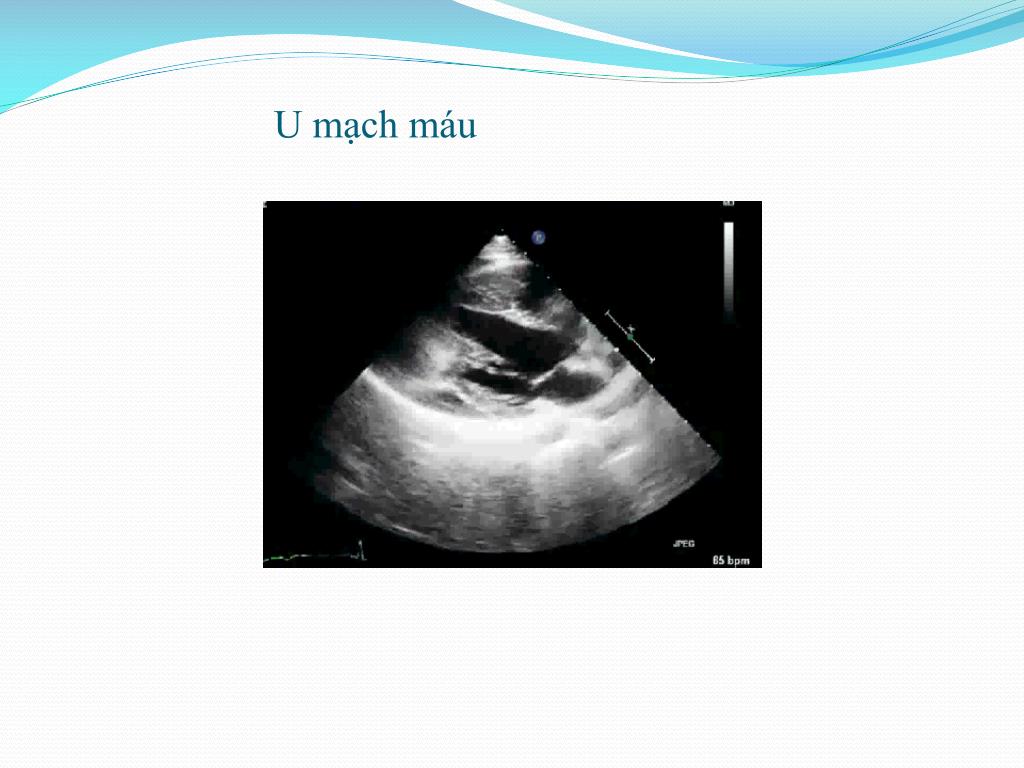

13. U mạch máu